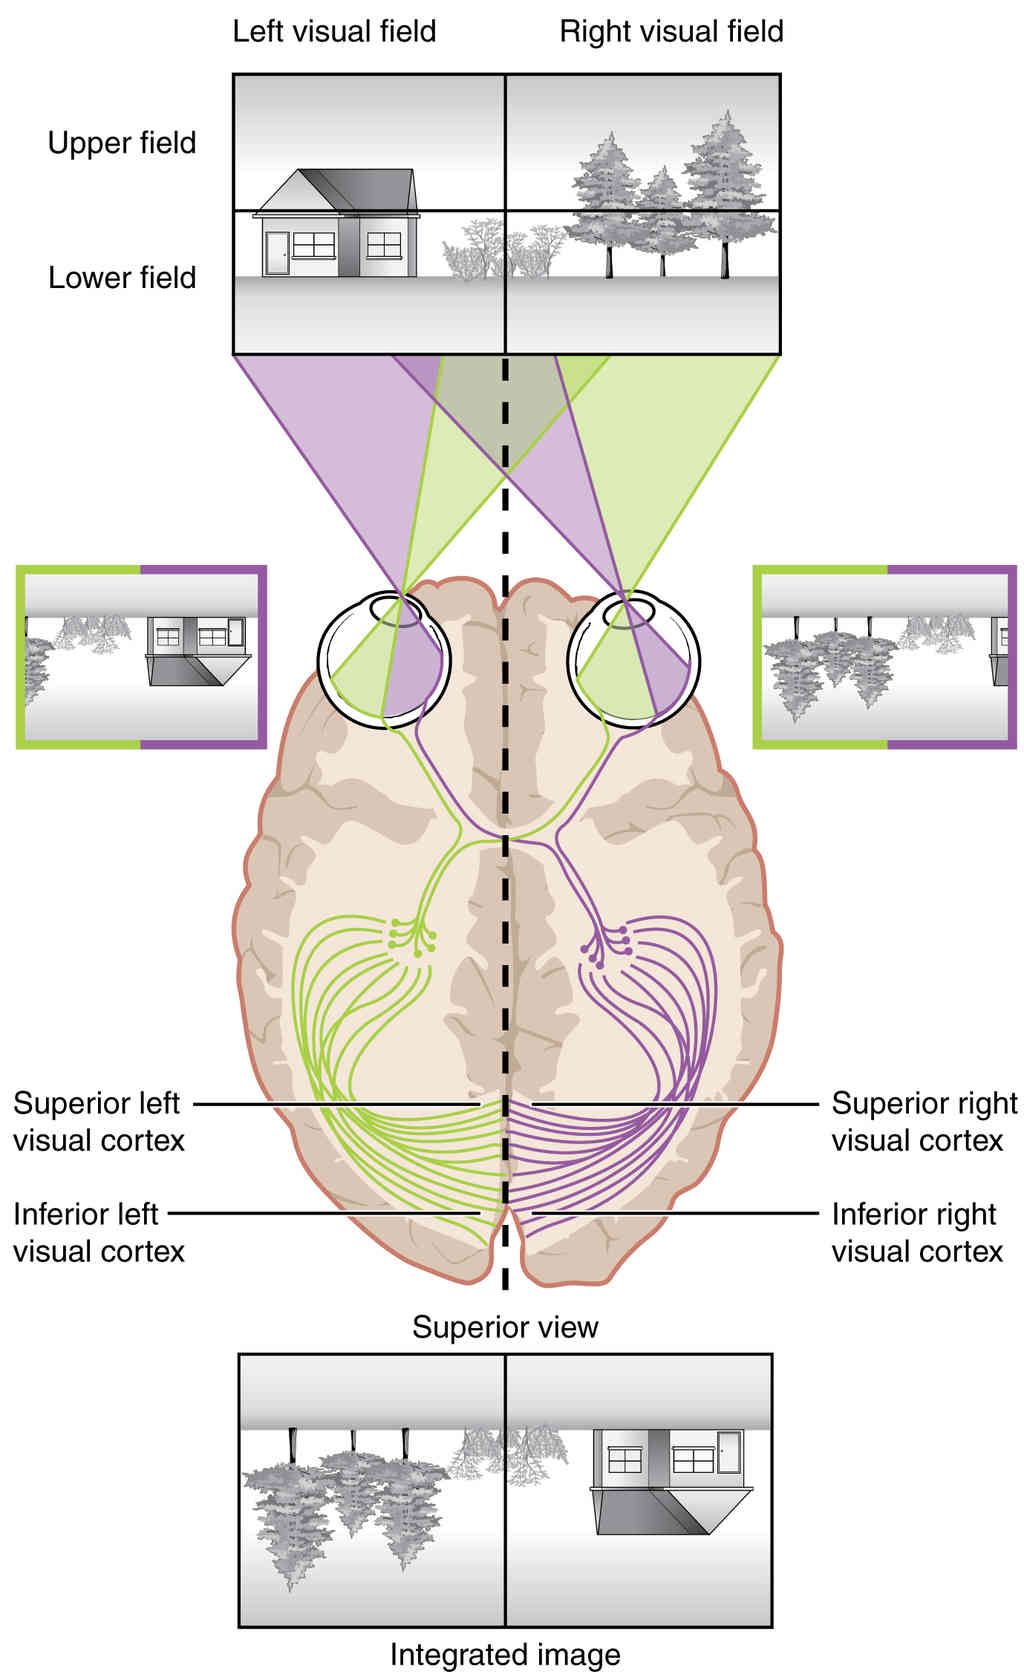

This page is under construction. For now, it is just a resource of the images found in the OpenStax Anatomy and Physiology Handbook. It wil slowly change into a revision tool. Each slide has a number. Use this to refer to the slide. When completed, it will have an unlabelled section, with labelled slides in parallel. On the unlabelled slides, write your answer and use the labelled slide to assess yourself. Keep track by also noting the number on each slide. Improvement at each attempt is important, more so than full marks on a first attempt.